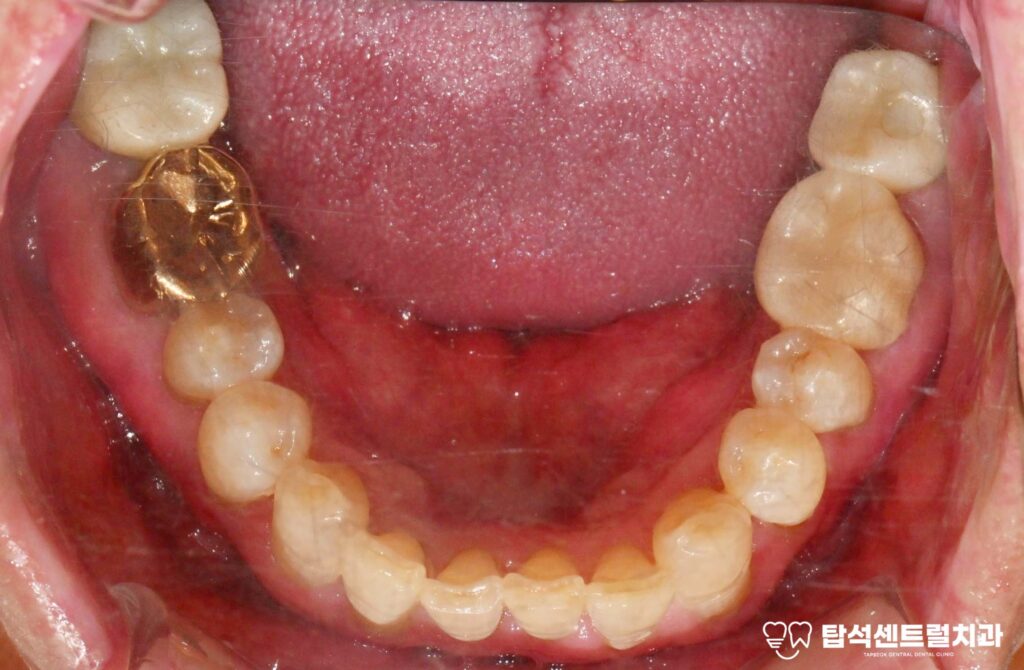

교합 관계가 맞지 않거나

잇몸 질환으로 인해

치조골이 약해진 경우에도

이가 이동하면서

공간이 발생하기도 합니다.

맞춤 계획의 중요성

구강 내 상태는 사람마다 다르기에

동일한 방법이 모두에게 적용되는 것은 아닙니다.

구강 건강 상태, 잇몸 상태, 교합 관계, 습관 등을

종합적으로 평가하여 개인에게

적합한 계획을 수립하는 것이 중요합니다.